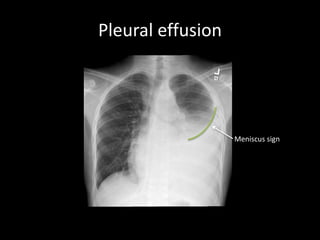

Pleural effusion

Meniscus sign